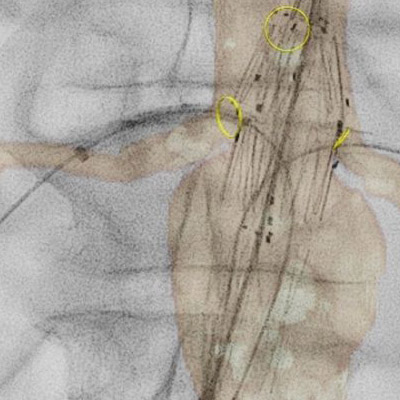

Wenn Sie ein bildgeführtes Verfahren durchführen, brauchen Sie eine zuverlässige Bildqualität – immer und zu jeder Zeit. AlluraClarity mit Philips ClarityIQ bietet Ihnen diese Bildqualität bei einer niedrigen Strahlendosis. In mittlerweile 18 klinischen „peer reviewed“ Studien weltweit wurde klar gezeigt: Mit dieser Technologie lässt sich eine 50-80% niedrigere Strahlendoses erreichen, und zwar bereichs-, patienten- und anwenderübergreifend*. Wir haben spontane Reaktionen aus der interventionellen Neuroradiologie, interventionellen Kardiologie, interventionellen Onkologie und Gefäßchirurgie gesammelt. Sie bestätigen uns, dass unsere Technologie bildgeführte Verfahren vereinfacht, das Dosismanagement für Patienten und Personal verbessert und die Zuverlässigkeit steigt.

Unsere Tools für Live-Bildführung unterstützen in Kombination mit Breitbild-Technologie modernste Verfahren durch eine intelligente und intuitive Integration modalitätenübergreifender Bilder am Behandlungsort, damit Ärzte zuverlässige Diagnosen stellen und das Verfahren in Echtzeit überwachen können.